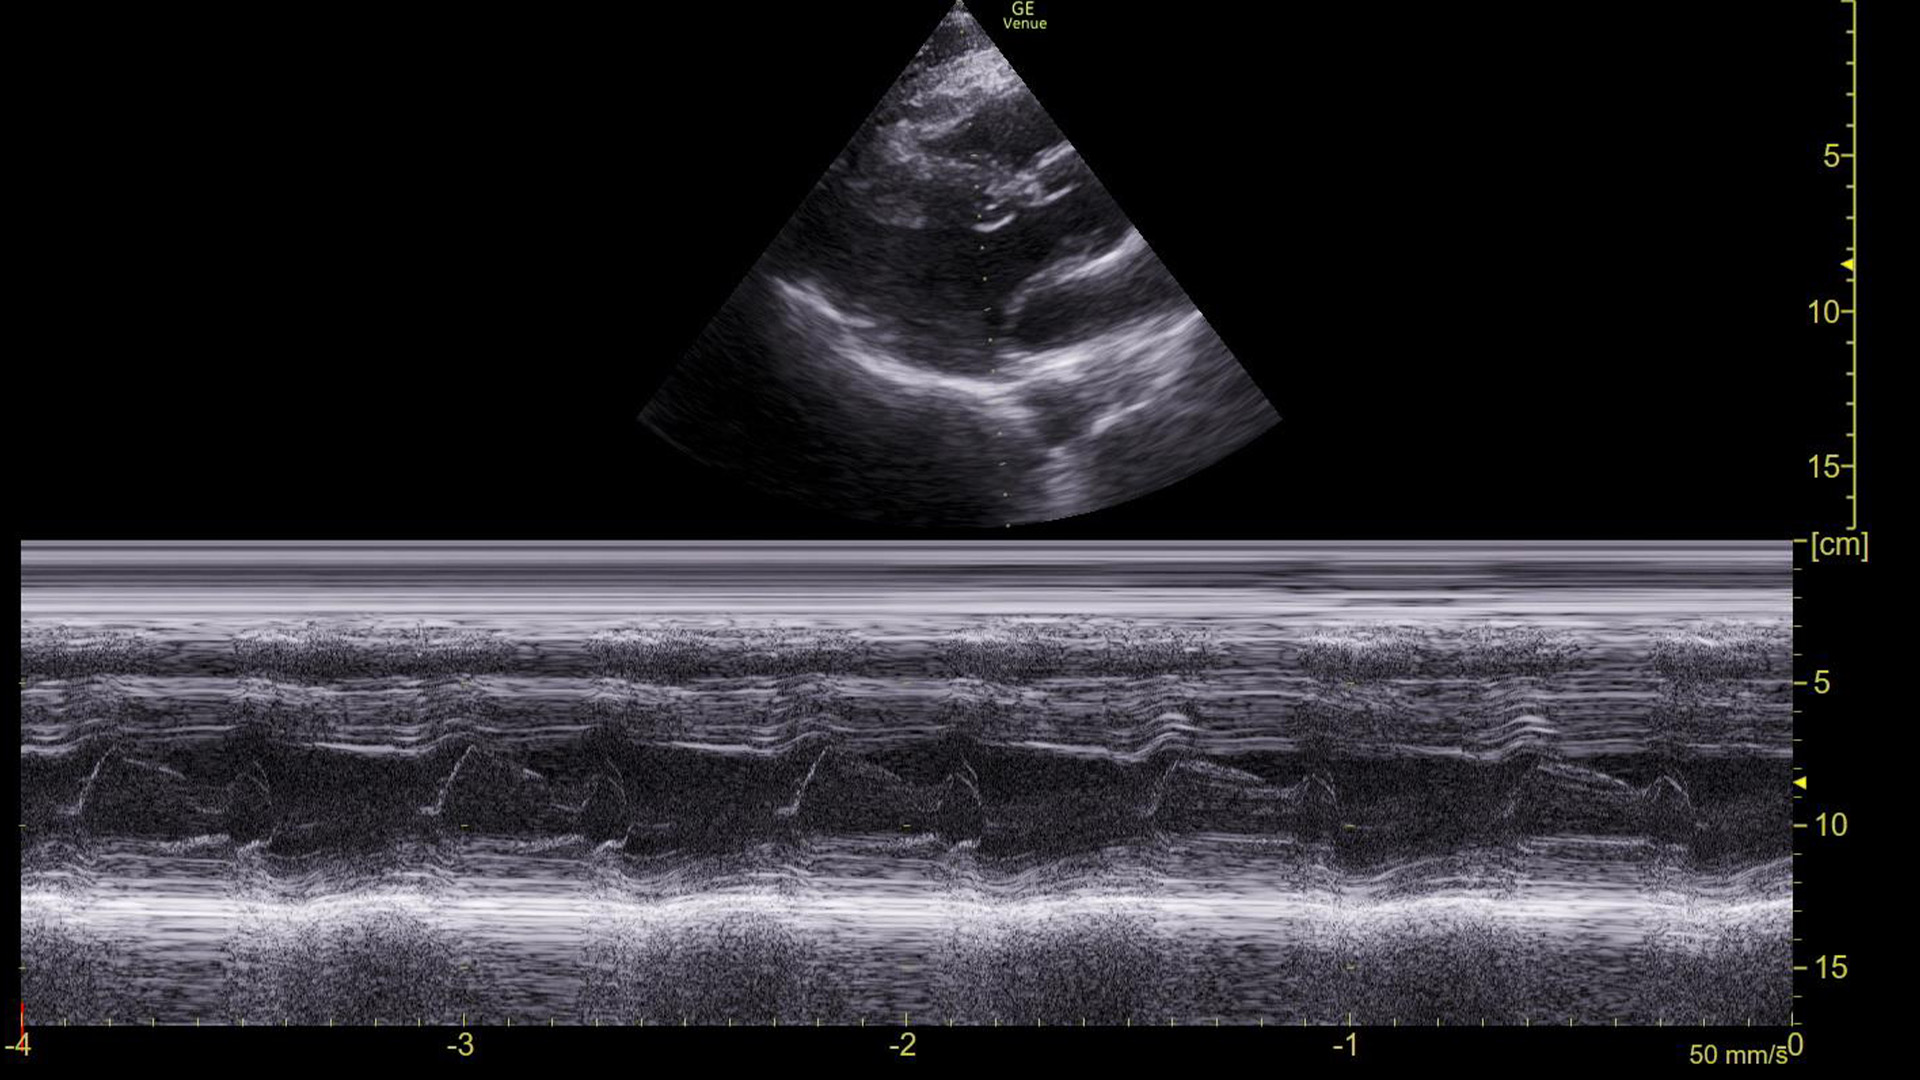

The machine read the ECG as sinus tachycardia, but I had my doubts. So, we obtained this M-mode tracing with the spike over the mitral valve in a parasternal long axis view.

Turn on M-mode and put the spike through the tips of the mitral valve

In a sinus rhythm, we see E-waves and A-waves. This is a normal appearing tracing.

M-mode

M-mode is a way to represent movement on a still image. To use it, a line (often referred to as a “spike”) is placed on a two-dimensional “B-mode” image. A recording is then made of the piece of the image under that spike over time. If nothing moved during the recording, it would produce a uniform/still tracing. However, if there is movement under the spike, it is visible on the tracing.